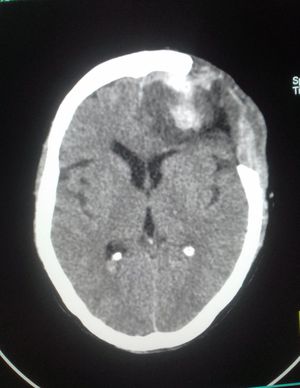

Tomography 👷

Looks like a tumor corroding the overlying bone. Glioblastoma?

Osteosarcoma of frontal bone invading frontal lobe of brain